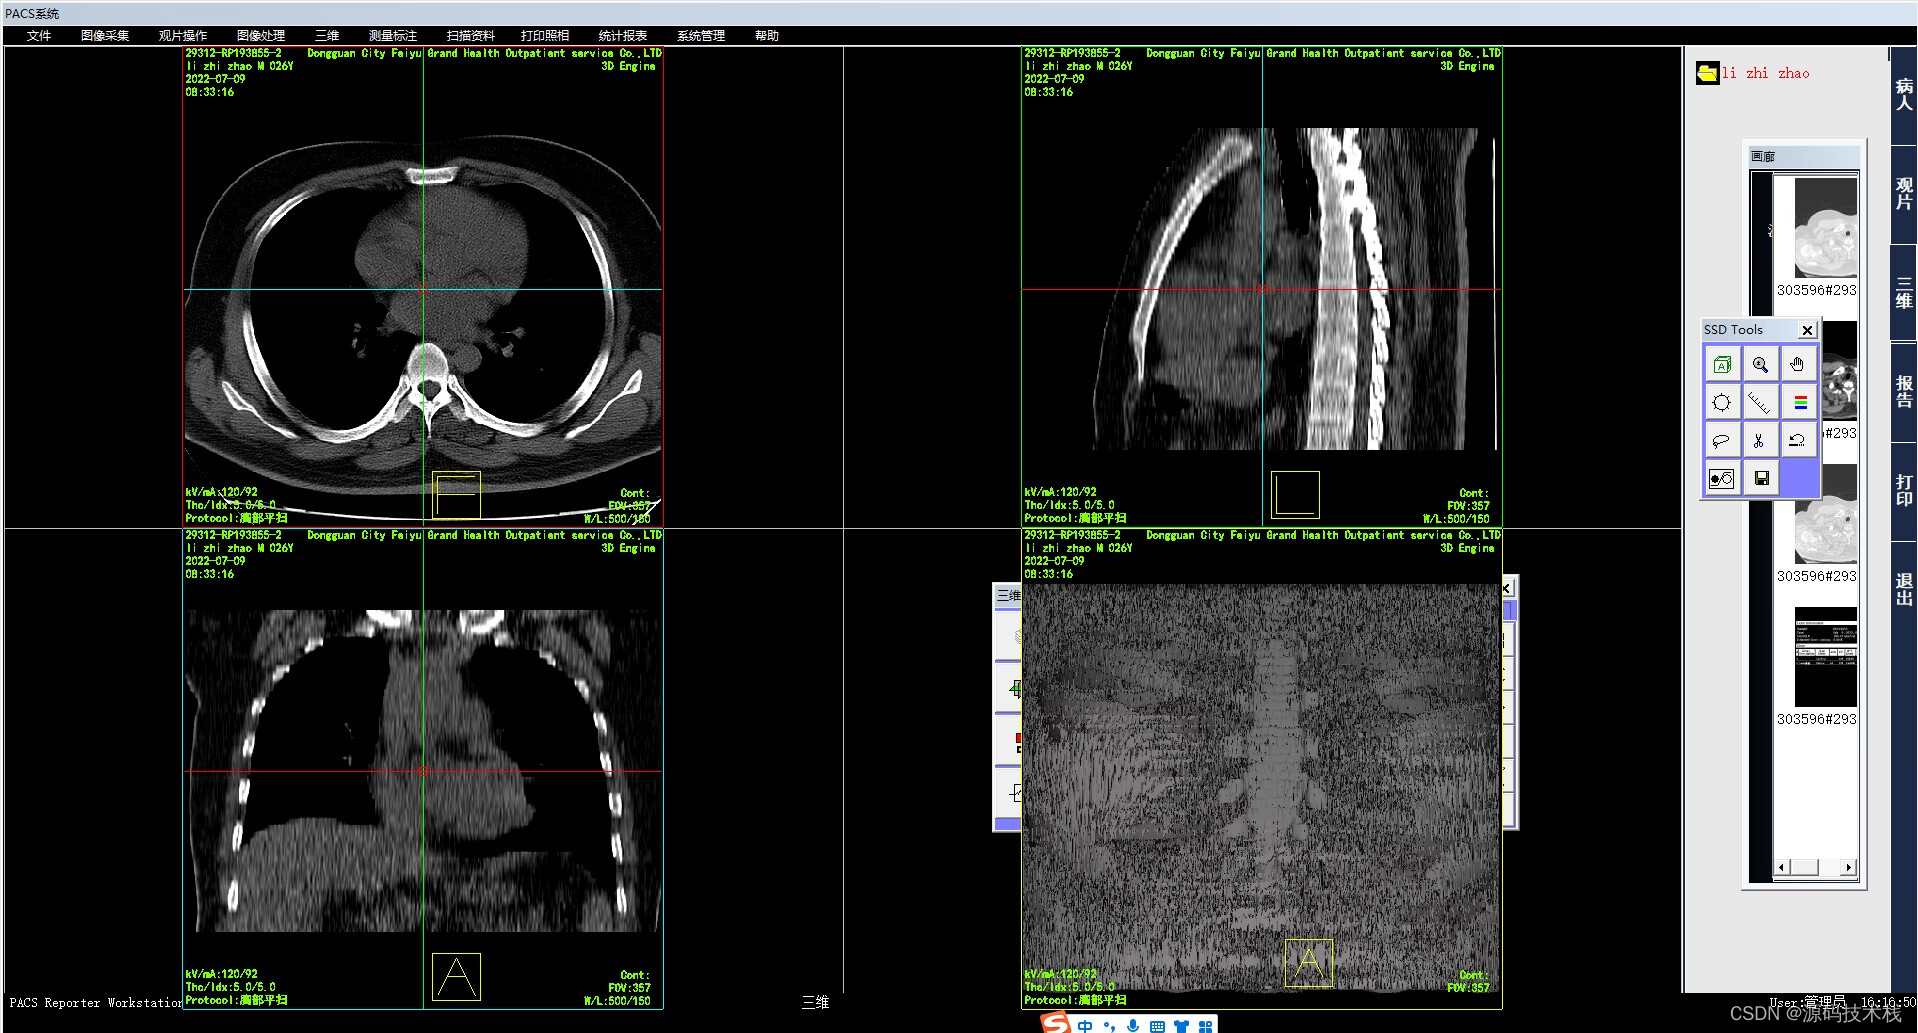

4、SSD

SSD(Surface Shaded Display),表面阴影遮盖,是将操作者的眼睛作为假设光源方向,投射到CT值在设定阈值以上的体素上则不再透过继续成像,仅呈现所有表面体素的集合立体图形,适用于显示CT值与其他结构相差较大的组织结构成像。简而言之,SSD图像就像是黑白的塑形图像,所以临床上主要用于显示骨骼病变或是结肠CT重建。